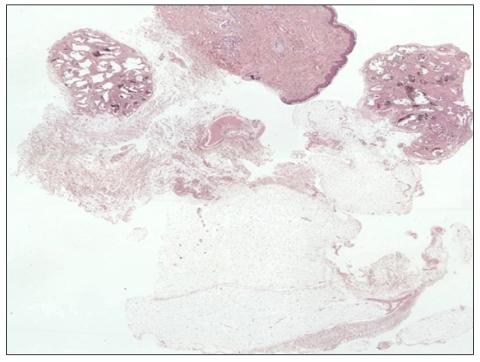

一例伴有脂肪瘤的窦状血管瘤。

A case of sinusoidal hemangioma with lipoma.

Sinusoidal hemangioma is a distinctive subset of a group of lesions known collectively as cavernous hemangiomas. Clinically, it develops in adults, predominantly females, and presents as a solitary, painless, bluish, deep dermal or subcutaneous nodule. Lipoma is the most common benign soft tissue tumor. Lipoma is distinguished from sinusoidal hemangioma on both clinical and histological grounds. Several studies have suggested that adipocytes originate from perivascular cells during adipogenesis. Angiogenic cytokines released by adipocytes play a role in the vasoproliferative response. The rearrangement or loss of chromosome 13 can also be associated with hemangioma. However, no previous cases of sinusoidal hemangioma have been associated with benign tumors like lipoma. Here, we describe an unusual case of sinusoidal hemangioma that occurred together with a lipoma on the right upper arm of a 43-year-old male.

摘要